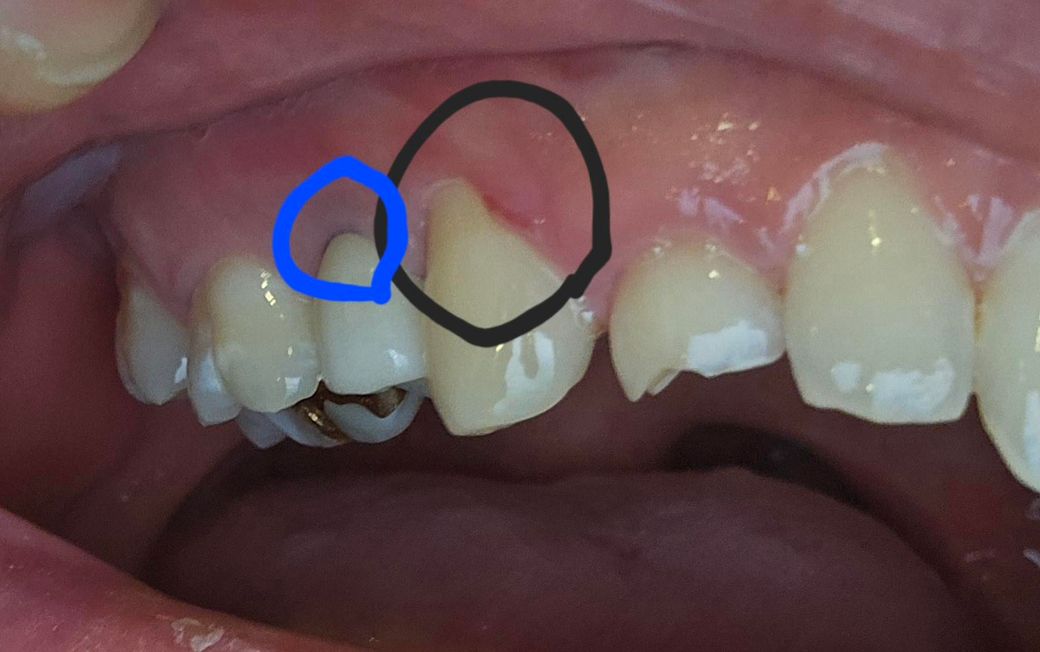

사진에 보시는 것과 겉이 검은색 동그라미 친 부분은 잇몸이 많이 벗겨져 치아가 많이 보이는 상태고, 한 ~ 두달 전부터 양치를 할 때마다 통증이 느껴집니다. 파란색 동그라미 친 부분은 임플란트를 3년 전에 했는데 검은색으로 보이더라구요. 저게 담배의 니코틴이 쌓여서 그런 건가요?

앞쪽 검은색으로 동그라미 친 부분은 잦은 양치로 인하여 잇몸이 내려가고 치아 뿌리가 노출된 것으로 보여집니다. 너무 많은 양치는 치아를 마모시킬 수 있습니다. 따라서 이러한 경우에는 치과 방문 후 양치 습관에 대한 상담이 필요합니다.

뒤쪽 파란색 부분은 임플란트 abutment 및 margin이 비춰 보이는 것입니다. 특별히 사용하는데 전혀 문제가 없습니다. 또한 잇몸이 얇다면 임플란트 내부 부분이 비춰 보일 수도 있습니다.

파란색 동그라미 친 부분은 임플란트를 3년 전에 했는데 검은색으로 보이더라구요. 저게 담배의 니코틴이 쌓여서 그런 건가요?

-> 잇몸이 퇴축되어 그렇습니다.

임플란트는 pfm 크라운으로 겉은 도자기색, 안쪽은 메탈인데 검은 선은 메탈이 비쳐보이는 것입니다